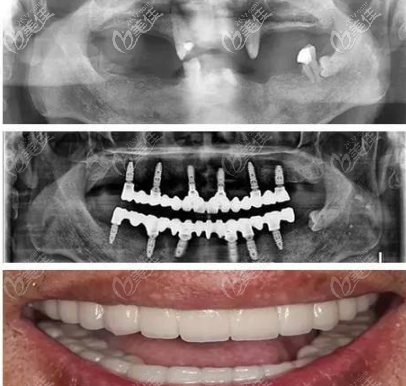

欣赏一个案例:

我爸爸做的是NobelSpeedy种植,已经65岁了,他是上下颌的牙齿加起来就剩3颗了,之前戴的义齿,但是口腔一直出血,弄的很难受,我一气之下,就给我爸爸做了种植。

老人真的不想花那么多钱,本来说选个便宜的种植体,但是我爸的条件本身就不好,怕选了便宜的还要出问题,就选的 NobelSpeedy的Shorty类型,我是趁着私立医院搞活动的时候做的,花了15万。